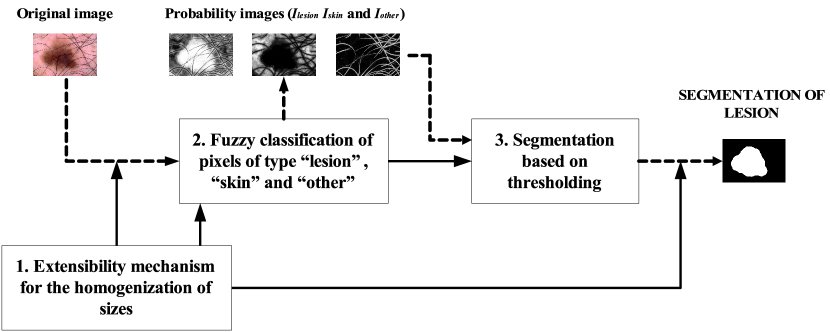

Below is shown the high level view of the system design, which is explained in detail in II-B, II-C and II-D. As can be seen in Fig. 1, it consists of the following modules: 1. Extensibility mechanism for the homogenization of sizes, in which the original images are resized in such a way that they may all end up having similar sizes as a way of starting Module 2, with the reverse process being carried out following execution of Module 3 in order for the size of the mask resulting from the sizes of the original image to be re-established; 2. Fuzzy classification of pixels of type “lesion”, “skin” and “other”, in which a fuzzy classification of pixels is made via supervised machine learning that enables the three corresponding fuzzy sets to be created , and and consequently the three probability images that map them out to be generated , and ; 3. Segmentation based on thresholding, in which different operations are carried out using these probability images to detect any disturbing artifacts and, therefore, segmentation of the pixels from the lesion and skin, and then applying a histogram thresholding method for segmentation of the lesion and a subsequent post-processing.